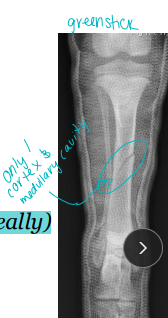

Tibia & fibula Fractures

Considerations: Common, Min soft tissue envelope, risk of open fracture

fibula broke concurrently, not broke in young

Tx:

Rx: Casting/splinting

closed, transverse fractures, >50% reduction, lateral splint (greenstick fractures)

Sx: Plate + screws, IM pin + cerclage, Interlocking nail, ESF